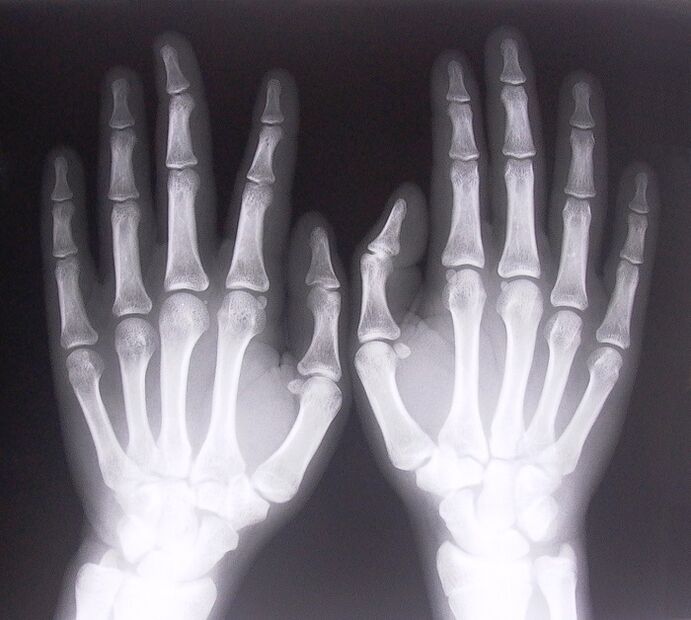

- გადაიღეთ რენტგენი.

- სტენოზირებული ლიგამენტიტი. დაავადების გამომწვევი მიზეზის დასადგენად აუცილებელია რენტგენის ჩატარება. დამახასიათებელია სიმპტომები: ხელის მტკივნეული მოძრაობა, დაჭიმული ხელის მოხვევა. ასევე, გაფართოების დროს, ჩვეულებრივ ისმის დაწკაპუნებები.